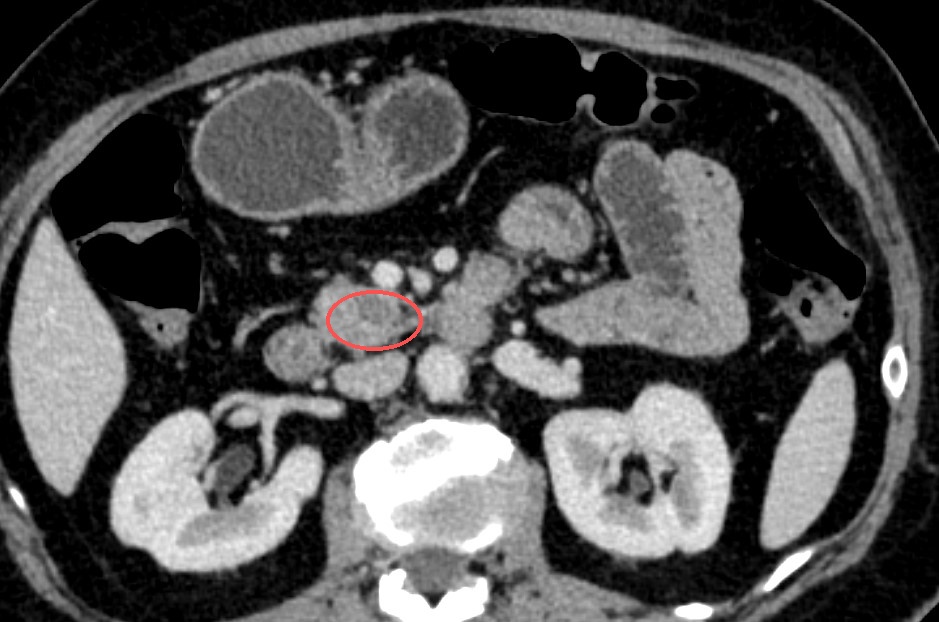

来院后,进一步的影像学检查揭开了这颗隐匿肿物的真面目:疑似胰腺实性假乳头状瘤,直径约2.5厘米,仅一枚一元硬币大小。“肿瘤与重要血管紧密交织,即便是在传统开腹手术的直视下,显露和分离都极其困难,稍有不慎就会面临难以控制的大出血。”程庆保主任介绍道。

胰腺钩突隐匿于腹腔极深处,不仅操作空间极其逼仄,紧密包绕着肠系膜上动静脉,更为众多的致命大血管所包绕。这里神经淋巴密集,肿瘤极易与周围脏器致密粘连,医生必须在极其狭小的缝隙里“走钢丝”,既要精准剥离血管、防范大出血,又要完成彻底的清扫,堪称外科手术的“生命禁区”。